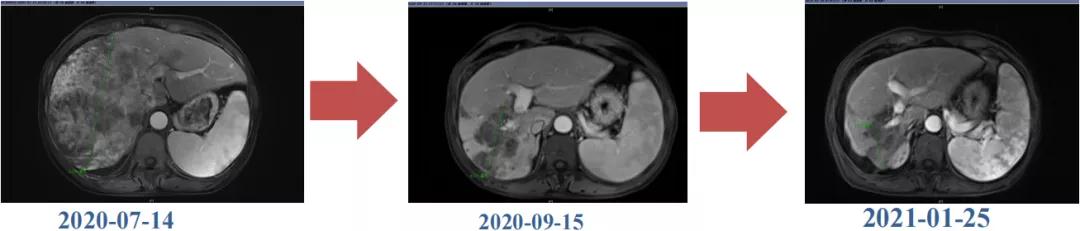

编者按:手术切除是肝癌最有效的治疗手段之一,但多数肝癌患者确诊时已处于晚期无法接受根治性手术。转化治疗已成为中晚期肝癌的重要治疗手段,可以通过局部和或系统治疗(如靶免治疗)将初始不可切除肝癌(uHCC)患者转化为可切除,从而改善患者预后。该病例为一例巨块型肝癌伴门脉癌栓形成合并肺转移,中国肝癌临床分期(CNLC)IIIb期,治疗前肿瘤最大直径18.4cm,通过接受仑伐替尼(乐卫玛®)联合信迪利单抗治疗后肿瘤降期,肝内病灶实现R0切除。患者目前OS已达17个月。

肝脏弹性超声:12kPa。腹部MRI平扫+增强:肝巨块结节性HCC(最大径18.4cm)伴肝内多发转移(最大径3.5cm),肝右静脉广泛癌栓形成;肝硬化伴门脉高压、脾大、少量腹水;肝囊肿;双肺多发转移。胸部CT平扫:两肺多发转移,两肺气肿伴肺大泡,两肺散在慢性炎症,右侧少量胸水。

Δ肝脏MRI,最大肿瘤18.4cm

肿瘤学评估(用药后2个月对比6个月):肝内主瘤明显缩小,动脉期强化降低;子灶消失;门脉右支癌栓明显缩小坏死;肺转移灶缩小,大部分消失。

Δ治疗过程中病灶影像学变化